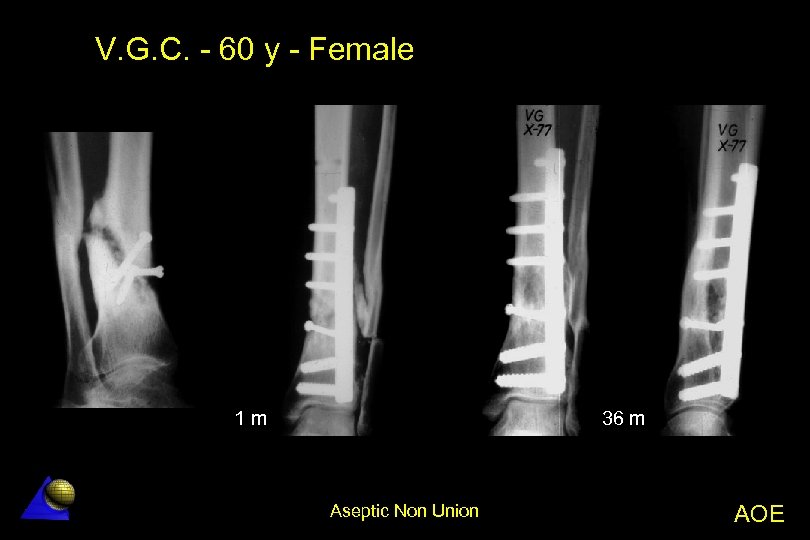

V. G. C. - 60 year old - Female Distal tibia non-union - 10 -74 Distal tibia fracture no-union l The fracture was treated in other Hospital l â Simple screw fixation without IF compression â No neutralization plate Lag screw and DCP plating with deformity correction l Bone healing in 2 months l Aseptic Non Union AOE

V. G. C. - 60 y - Female PO 1 m Aseptic Non Union AOE

V. G. C. - 60 y - Female 1 m 36 m Aseptic Non Union AOE